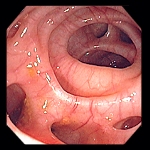

Ce que l'on observe lors d'une coloscopie

![]() |

Colon transverse

|

Bas fond coecal

et sa valvule de Bauhin en bas à gauche |